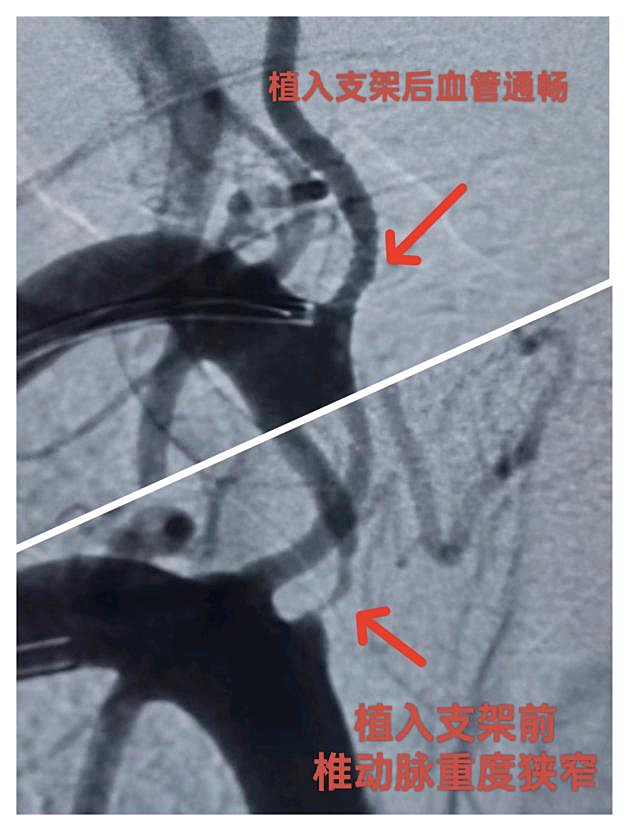

是心脏更重要还是大脑更重要?答案是都重要!广西科技大学第一附属医院胸痛中心、卒中中心联合启动导管室,立即为患者行一站式心脑血管造影,造影显示患者冠脉血管有狭窄但已再通,考虑是用药后血管再通,而脑动脉造影显示患者右椎动脉狭窄达99%!根据泛血管管理中心多学科会诊机制,经心血管内科、神经内科、导管室联合会诊商讨决定,考虑冠状动脉用药后血管再通,患者目前右椎动脉病变更严重,优先处理椎动脉病变,于是在术中经桡动脉入路于右椎动脉开口处为患者植入支架一枚,解除血管狭窄,全程只有右侧桡动脉一个穿刺点。术后患者胸痛已缓解,恢复言语后马上转到心血管内科接力救治,并于5天后经鼻烟壶区远端桡动脉穿刺入路完成右冠脉严重狭窄段支架植入术。这是我院首例经桡动脉入路椎动脉支架植入术,患者术后恢复更快、体验更佳。